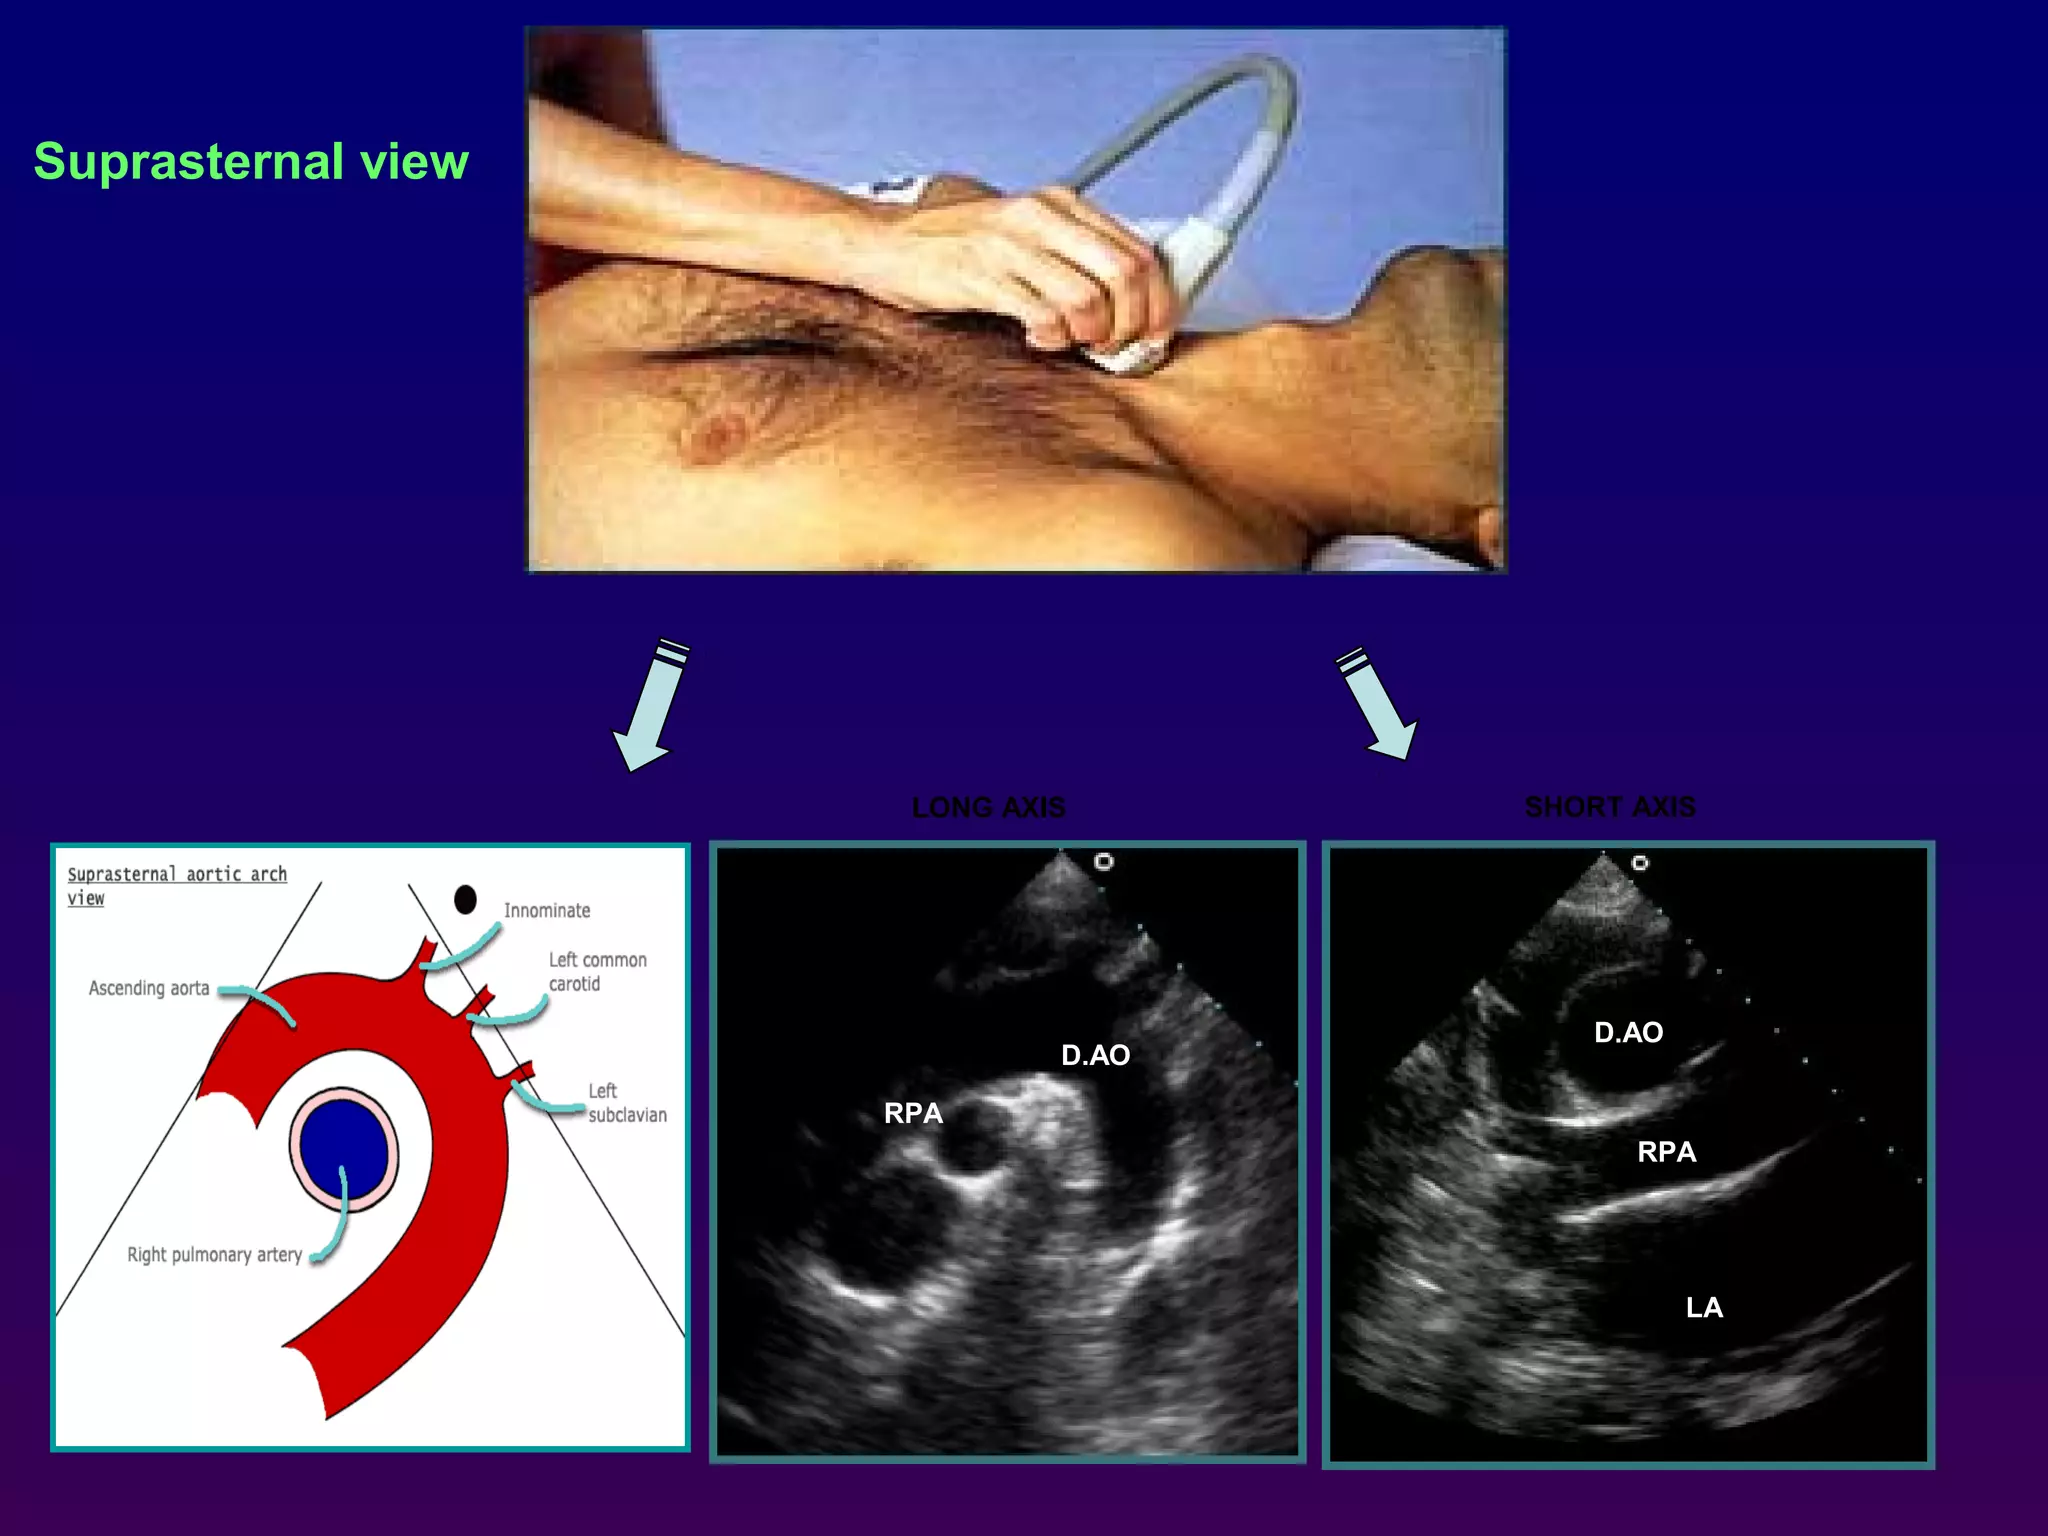

Suprasternal view

With the patient supine and the neck extended, the

transducer is placed in the suprasternal notch to

obtain a long-axis image of the distal ascending,

transverse, and proximal descending aorta.

The take- off of the left carotid and left subclavian

artery may also be appreciated. Centrally positioned

and "beneath" the aortic arch is a short-axis of the

right pulmonary artery This view may be particularly

valuable for the evaluation of suspected patent

ductus arteriosus, aortic coarctation, or aortic

dissection.

LONG AXIS SHORT AXIS

LA

Suprasternal view With thepatient supine and the neck extended, the transducer is placed in the suprasternal notch to obtain a long-axis image of the distal ascending, transverse, and proximal descending aorta. The take- off of the left carotid and left subclavian artery may also be appreciated. Centrally positioned and "beneath" the aortic arch is a short-axis of the right pulmonary artery This view may be particularly valuable for the evaluation of suspected patent ductus arteriosus, aortic coarctation, or aortic dissection. AV A.AO